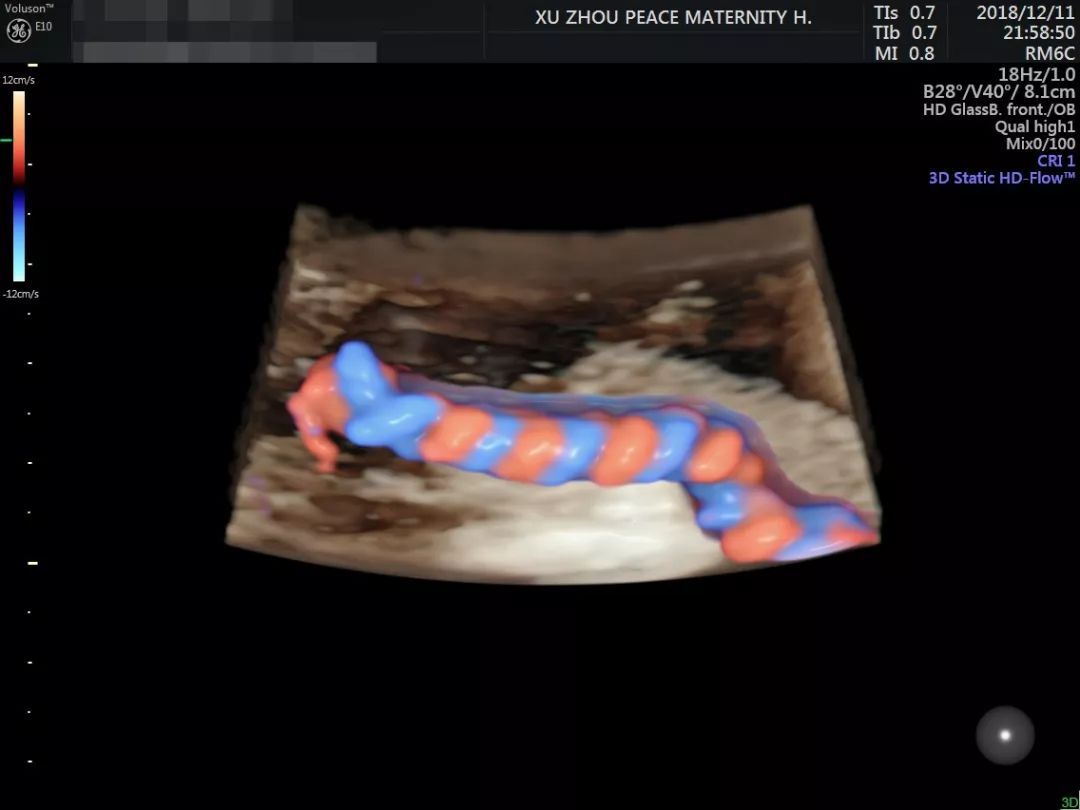

这其中既有妈妈和宝宝的原因

(比如妈咪子宫较厚、羊水清晰度不够

或者胎宝宝蜷缩着身体、小手挡住了脸)

也有四维设备与专家的原因